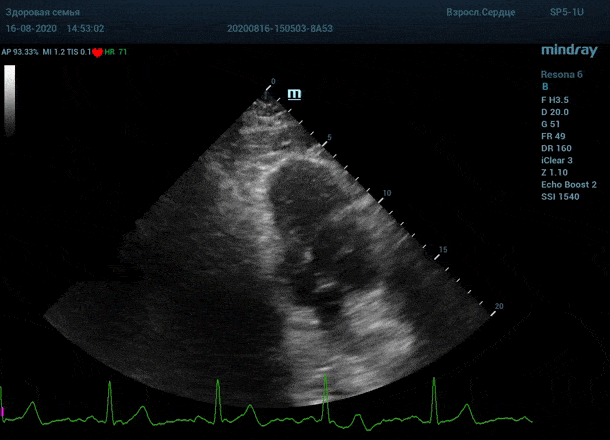

Обзор функции УЗИ: адаптивный колорайзинг

"Трудные пациенты" в эхокардиографии - явление не редкое. Часто встречается деформация грудной клетки или же площадь поверхности тела очень большая. Проблема акустического окна решается сменой положения тела пациента, снижением частот, изменением динамического диапазона и применением уникальных технологий производителя оборудования. Когда возможности ультразвуковой машины по оптимизации изображения исчерпаны, на помощь приходит оптимизация органа зрения.

Глаз каждого человека по своей природе уникален. Одни люди лучше видят белый и серый цвет, прекрасно различают все его оттенки. Другим людям проще ориентироваться в голубом, синем и фиолетовом диапазоне, холодных тонах изображения. Однако большинство прекрасно видит оранжевый цвет, и очень четко отличает его от черного – анэхогенного пространства.

Адаптивный колорайзинг - настоящая находка для опытного врача ультразвуковой и функциональной диагностики. Для тренированного глаза открывается новый мир четких контуров, совершенно другой взгляд на привычные структуры сердца.

Данная функция присутствует в большинстве моделей Mindray, с возможностью эхокардиографического исследования. Ограниченное ЭХО окно можно победить разными путями.